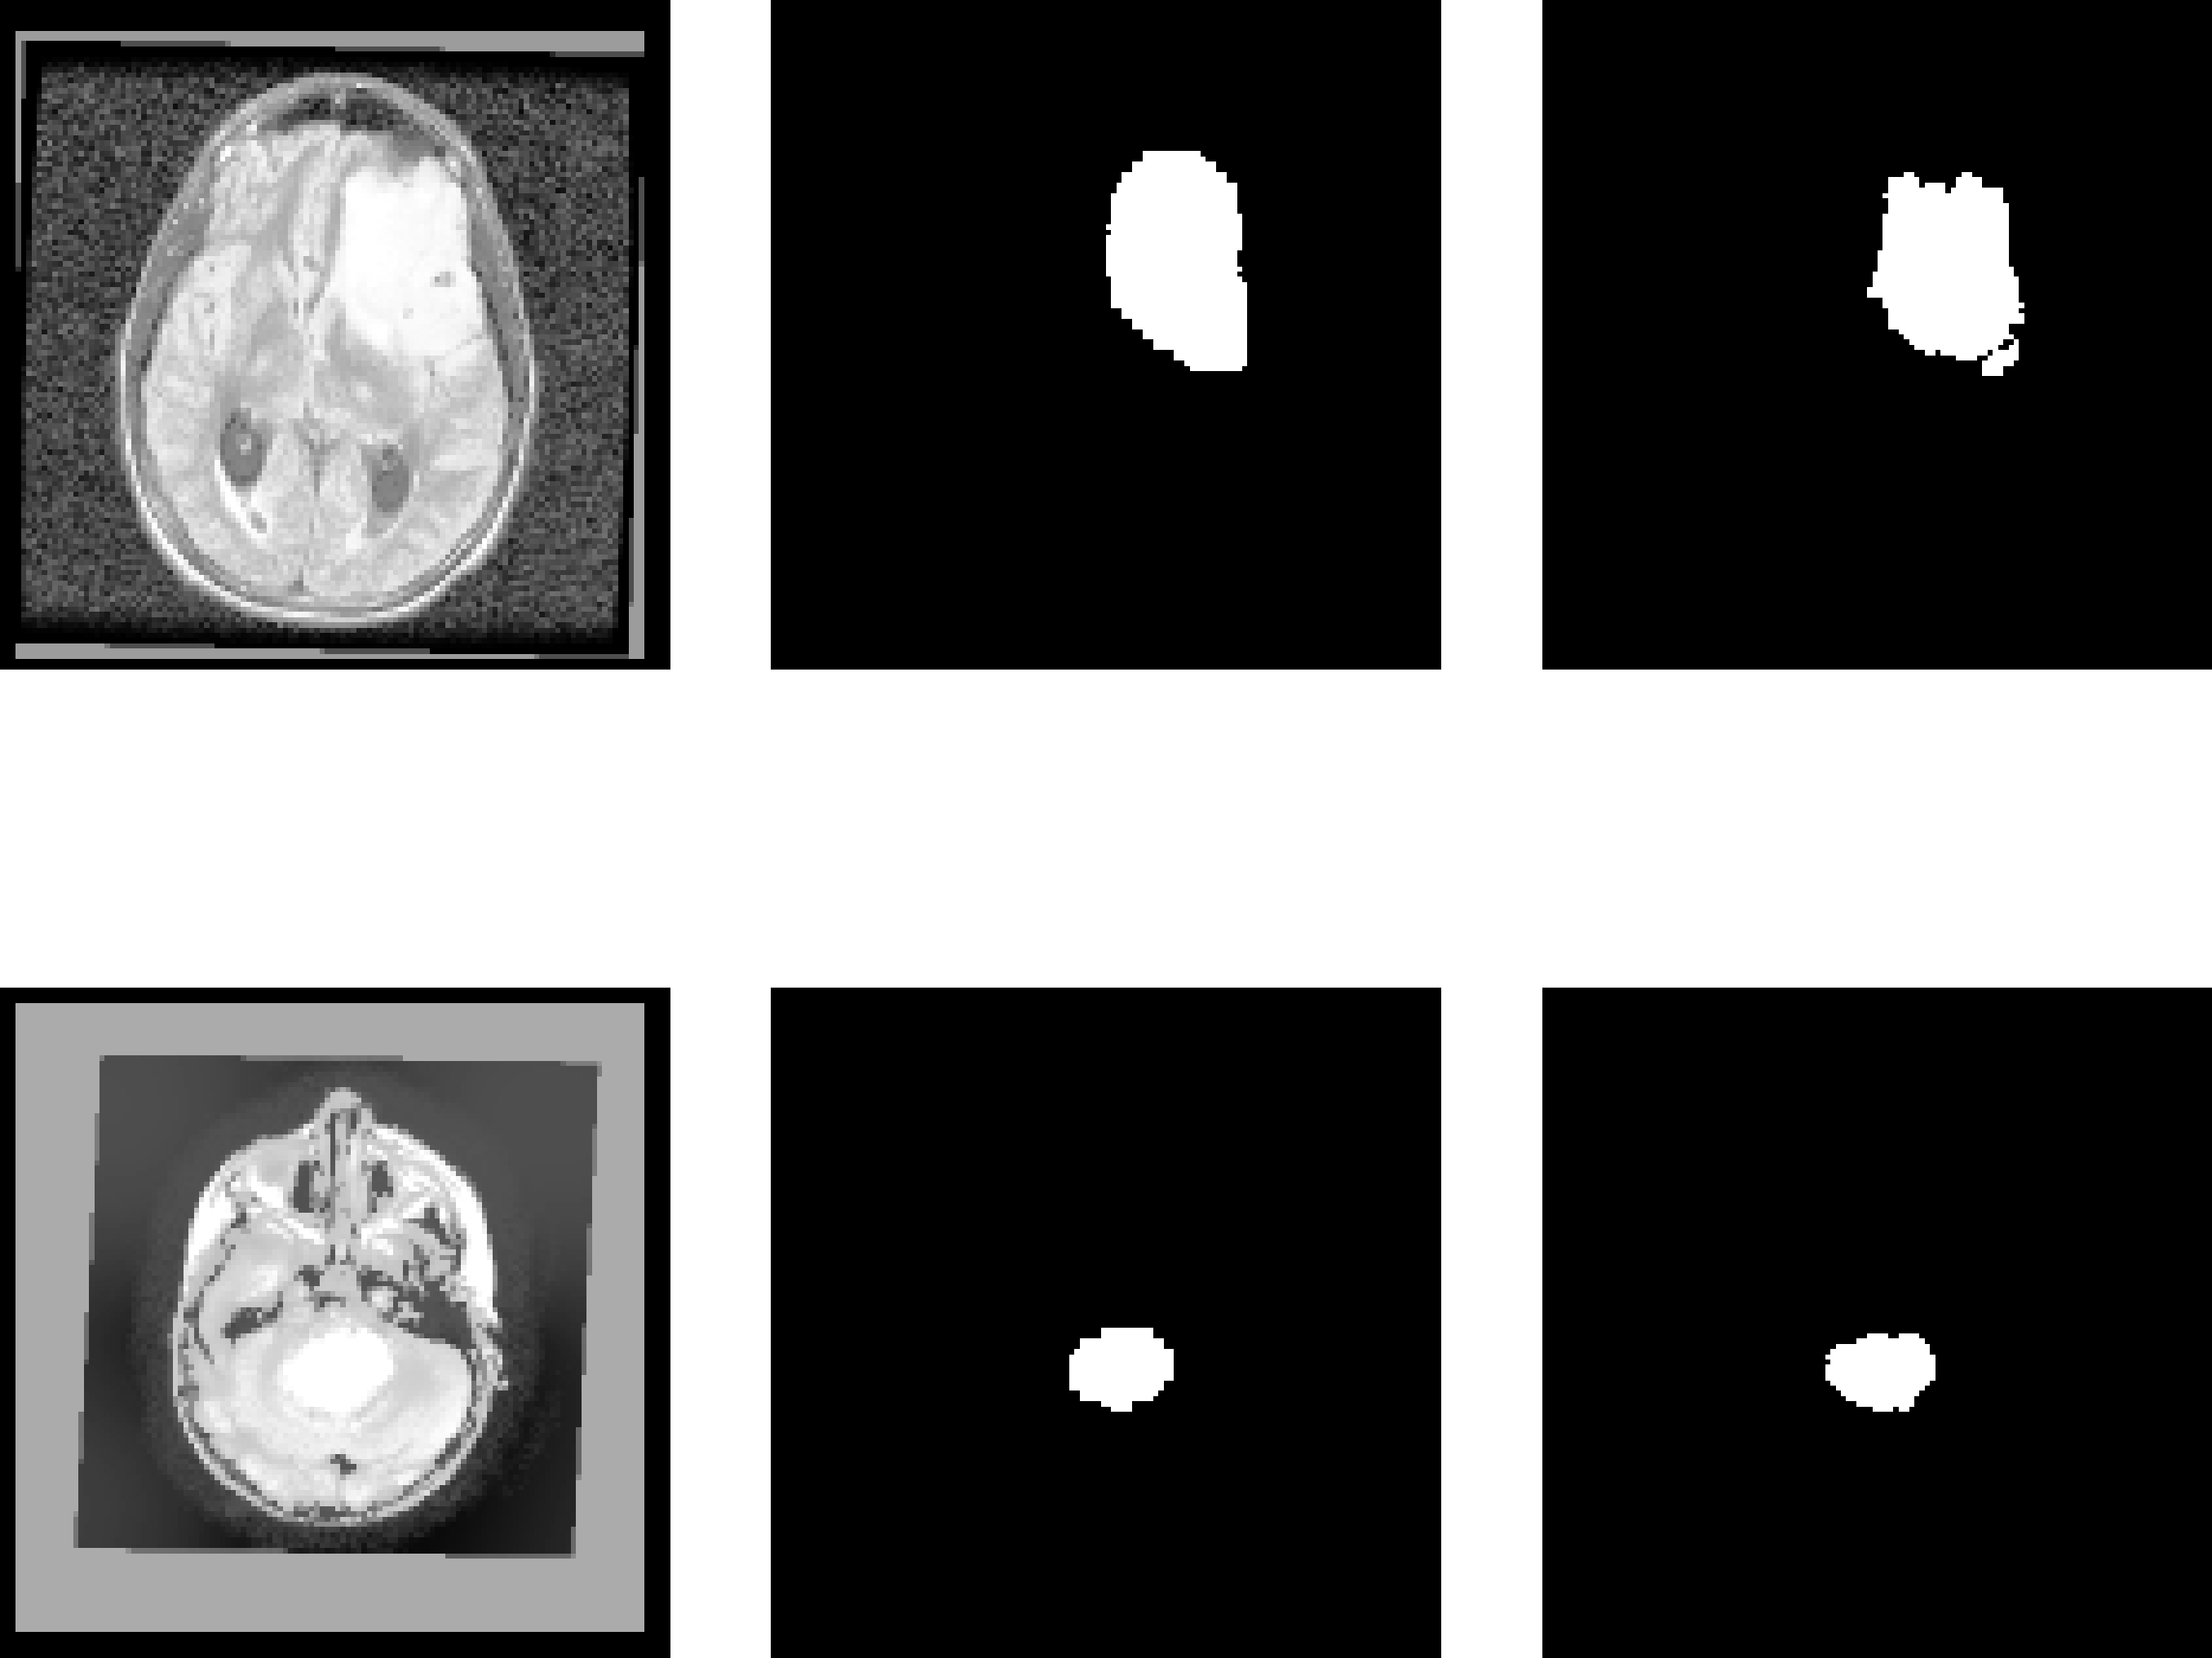

Examples of cancerous MR images and their generated non-cancerous variants are presented in Figure 5. Examples of cancerous MR images, their generated segmentations, and their true segmentations are visualized in Figure 6.

Refer to caption

(a) Examples from BraTS dataset.

(b) Examples from PLGNT dataset.

Fig. 6: MR image FLAIR channel (left), model segmentation (middle), true segmentation (right).